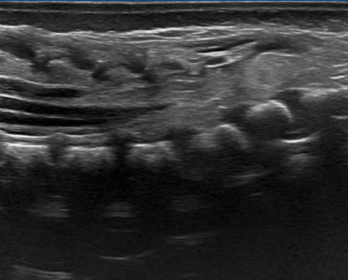

Ecografia de caderas

Estudio esencial en bebés para detectar displasia del desarrollo de cadera. Es indolora y se realiza idealmente en los primeros meses de vida como parte del control del niño sano.